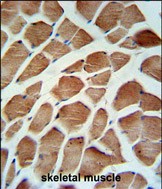

- CA5B Antibody (C-term) (Cat. #P30489) IHC analysis in formalin fixed and paraffin embedded human skeletal muscle followed by peroxidase conjugation of the secondary antibody and DAB staining. This data demonstrates the use of the CA5B Antibody (C-term) for immunohistochemistry. Clinical relevance has not been evaluated.